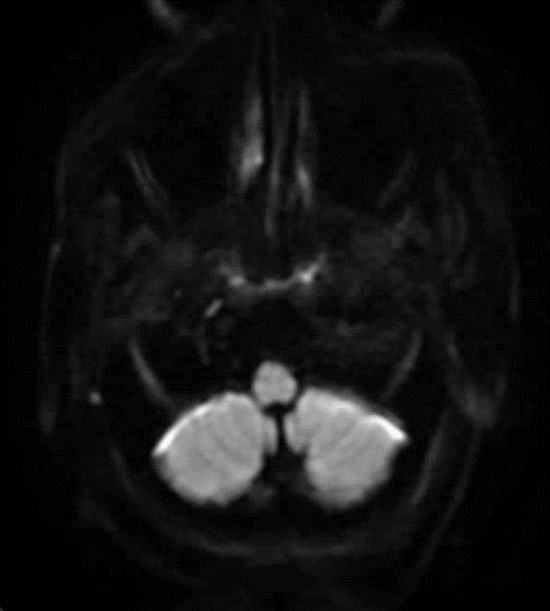

急诊头颅MRI+MRA示:双侧额叶少许小缺血灶;脑动脉硬化,伴左侧大脑前动脉纤细及多组脑动脉局限性狭窄。

CTP示:右侧额颞顶枕叶、左侧额叶Tmax稍延长,提示侧枝代偿尚可。

DSA:

3D测量。

90cm 长鞘+5F 125cm Tethys®中间导引导管,Synchro支撑力不足,更换3m 0.014inch微导丝。

引入加奇1.75×9mm SacSpeed®球囊扩张导管。

预扩张后造影。

引入支架微导管,确认位置。

引入4.0×39mm支架,支架释放后由于张力后退。

无法回收支架,完全释放。

支架中部再狭窄明显,导丝成袢确认位于支架内并引入加奇2.25×12mm SacSpeed®球囊扩张导管。

加奇2.25×12mm SacSpeed®球囊到位并扩张。

后扩后复查造影。